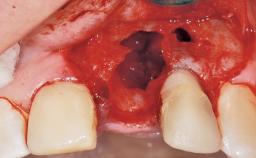

Immediate Placement of an Implant in a Maxillary Left Central Incisor Site

A 33-year-old female patient presented with an upper left central incisor that required extraction after a failed endodontic therapy. The tooth had been traumatized when the patient was a teenager and had undergone several endodontic treatments, including two apicectomy procedures. The patient was in good health and did not smoke. Clinical examination showed that the patient had a high lip line. In full smile, the gingival margins of the upper teeth were visible to the first molars. The gingival margins of central incisors 11 and 21 were only just showing. Examination of tooth 21 confirmed that the tooth was mobile and had hypererupted by 1 mm.

| Placement Protocol | Immediate implant placement |

| Tooth Site | Maxillary incisor or canine |

| Socket Morphology | Single-root socket |

| Socket Integrity | Damage to one or more bone walls |